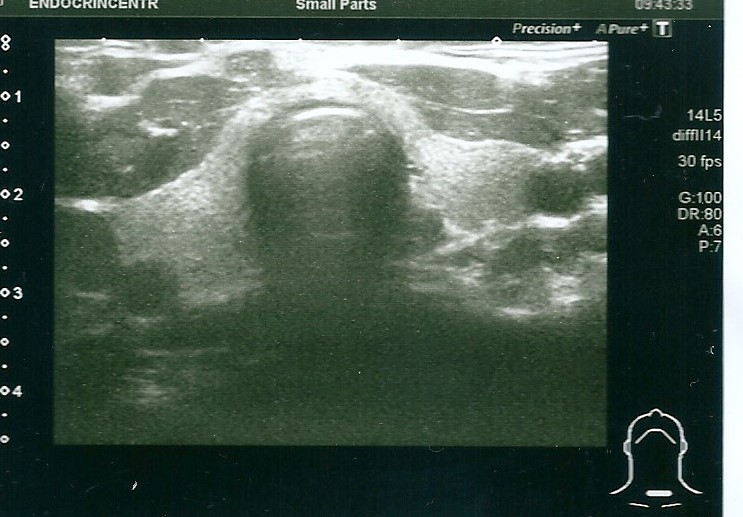

В 35 лет пациентка поступила в НМИЦ эндокринологии с жалобами на судорожный синдром. При осмотре обращали на себя внимание низкорослость (рост 148 см), ожирение (87 кг, ИМТ 39) с лунообразным лицом, брахидактилия (рис. 4, 5), подкожные кальцинаты, положительный симптом Хвостека. При сжатии кистей в кулак отмечалась сглаженность в области IV–V пястно-фаланговых суставов – брахиметафалангизм (рис. 6). В ходе обследования была выявлена декомпенсация по кальций-фосфорному обмену и гипотиреозу: гипокальциемия (Са ион. 0,87 ммоль/л при норме 1,03–1,29), гиперфосфатемия (1,81 ммоль/л при норме 0,74–1,52), повышение уровня ПТГ до 136 пг/мл (15–65), гипотиреоз (ТТГ 7,37 мМЕ/л при норме 0,64–5,76, св.Т4 8,72 пмоль/л при норме 11,5–20,4) при нормальном уровне аутоантител (АТ) (АТ к тиреопероксидазе (ТПО) 1,77 МЕ/мл, при норме 0–5,6) и отсутствии эхо-признаков аутоиммунного тиреоидита по данным УЗИ щитовидной железы (рис. 7). В суточном анализе мочи гипокальциурия 0,804 ммоль/сут (2,5–8), 0,37 мг/кг/сут, гипофосфатурия – 12,52 ммоль/сут (13–42). Беседа с пациенткой выявила ряд психологических проблем, появление которых сама женщина связывала с тяжелым переживанием последнего аборта: на фоне депрессии перестала следить за питанием и регулярным приемом препаратов, отмечались прогрессирующий набор веса и периодическая боль в мышцах, развившаяся в итоге в карпопедальный спазм. Проявления острой гипокальциемии были купированы введением раствора кальция глюконата; показатели кальций-фосфорного обмена и функционального статуса щитовидной железы нормализовались после восстановления и коррекции приема альфакальцидола и левотироксина натрия. По поводу имеющейся депрессии получает антидепрессанты под наблюдением психоневролога.

Рис. 7. Отсутствие эхографических признаков аутоиммунного поражения щитовидной железы